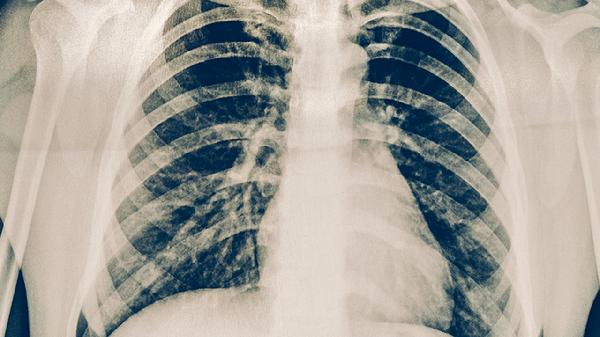

肺结核可通过抗结核药物治疗、手术治疗、营养支持治疗、心理干预及隔离防护等方式治疗。肺结核通常由结核分枝杆菌感染引起,表现为咳嗽、咯血、低热等症状,需遵医嘱规范治疗。

对于药物治疗无效的慢性纤维空洞型肺结核、结核性脓胸或大咯血患者,可考虑肺叶切除术或胸膜剥脱术。手术前需完成至少2-3个月的强化抗结核治疗,术后仍需继续用药6-18个月。手术能清除病灶但存在出血、支气管胸膜瘘等风险,需由胸外科医生评估指征。术后应加强呼吸功能锻炼,定期复查胸部CT评估恢复情况。